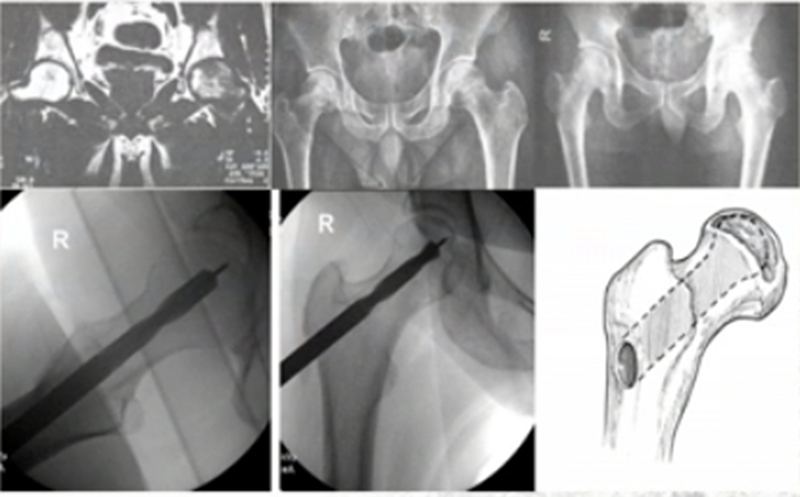

但通过髓芯减压联合钽棒及干细胞移植,仍有部分患者保髋失败,一项研究表明,3年失败率达10%。笔者团队通过收集对照组和手术保守失败的股骨头标本,统计发现>33.5%的样本存在股骨头帽状分离(CSS),即软骨-软骨下骨间出现微骨折和(或)囊性变,MRI TW2显示软骨-软骨下骨间高信号条带影。这种情况称为“假2真3”期,要充分关注到股骨头坏死不仅仅是骨的问题,还要关注软骨的问题。

为进一步探析软骨帽状分离,笔者团队对股骨头软骨也进行进一步的研究,提出“腾起术”,是将外科脱位、清除死骨打压植骨、股骨头软骨面修复技术结合,恢复股骨头原有外形,主要针对年轻ⅢB期股骨头塌陷患者。